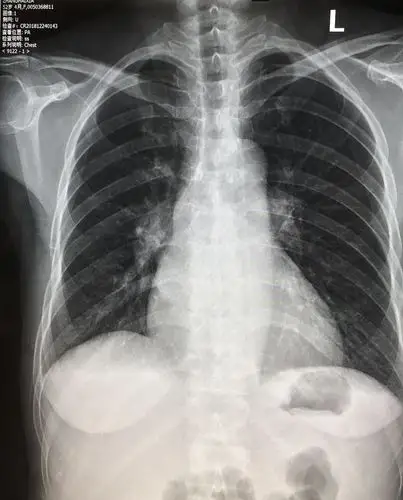

注意右侧心膈角,右下叶不张  的诊断成立.影像科的大夫会看图说话